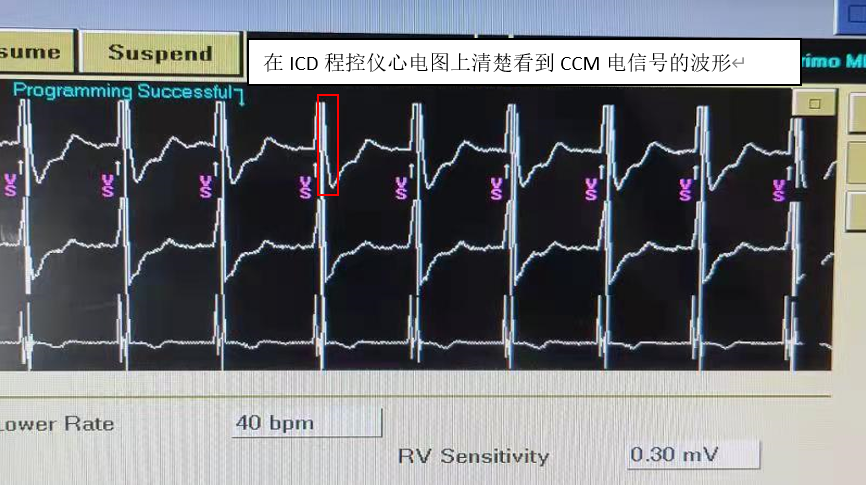

ICD程控仪界面:

图片